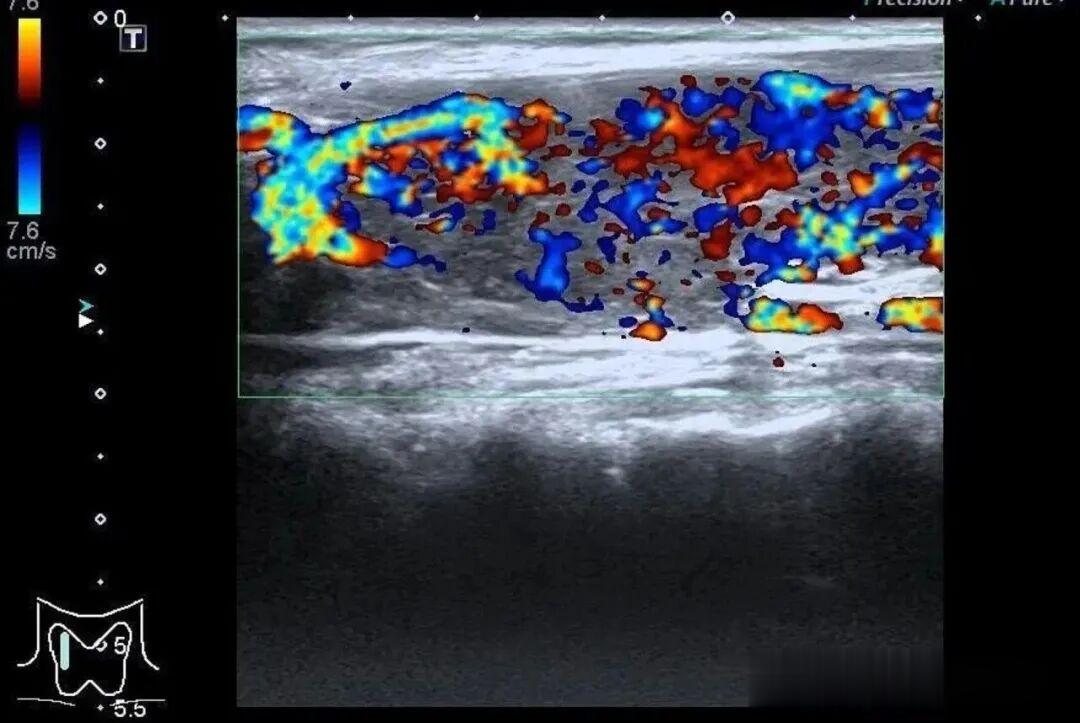

而更致命的隐患藏在她的病史里——陈女士是一位有着20年甲亢病史的患者,并且已经自行停药一年。鉴于病情危重,陈女士被紧急转入瑞金医院卢湾分院内分泌科。

甲状腺功能检查中,游离T3高达20.83pmol/L(正常值3.5-6.5pmol/L),游离T4高达88.42pmol/L(正常值11.5-22.7pmol/L),这两项核心激素都超过正常上限数倍,而本应调控它们的促甲状腺激素(TSH)却几乎测不出来,这明确证实了陈女士患有极其严重的甲状腺毒症。心脏超声结果同样不容乐观,射血分数仅有40%(正常应高于55%),这意味着心脏泵血能力大幅下降。

同时,CT检查发现她的双侧胸腔、腹腔存在积液。综合各项检查结果,医生判断陈女士患上了甲状腺危象,这是甲亢最凶险的并发症。